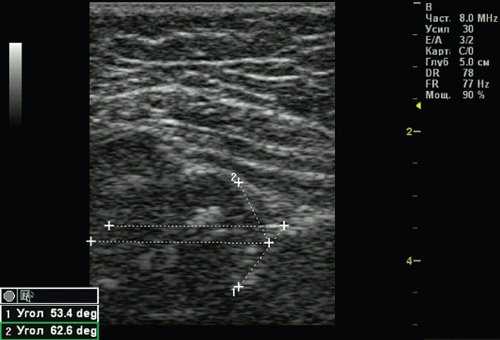

Тип 2б тазобедренных суставов выявлен у 25 (6,33%) детей - дисплазия тазобедренных суставов у детей старше 3 мес (рис. 4). Костная вертлужная впадина недостаточно развита, костный эркер закруглен, костнохрящевое соотношение меньше 2/3, хрящевая часть крыши охватывает головку бедренной кости. Угол α меньше 59°, но больше 50°, угол β больше 60°.

Рис. 4. Тазобедренный сустав тип 2б.

1 - угол α=53,4°;

2 - угол β=62,6°.